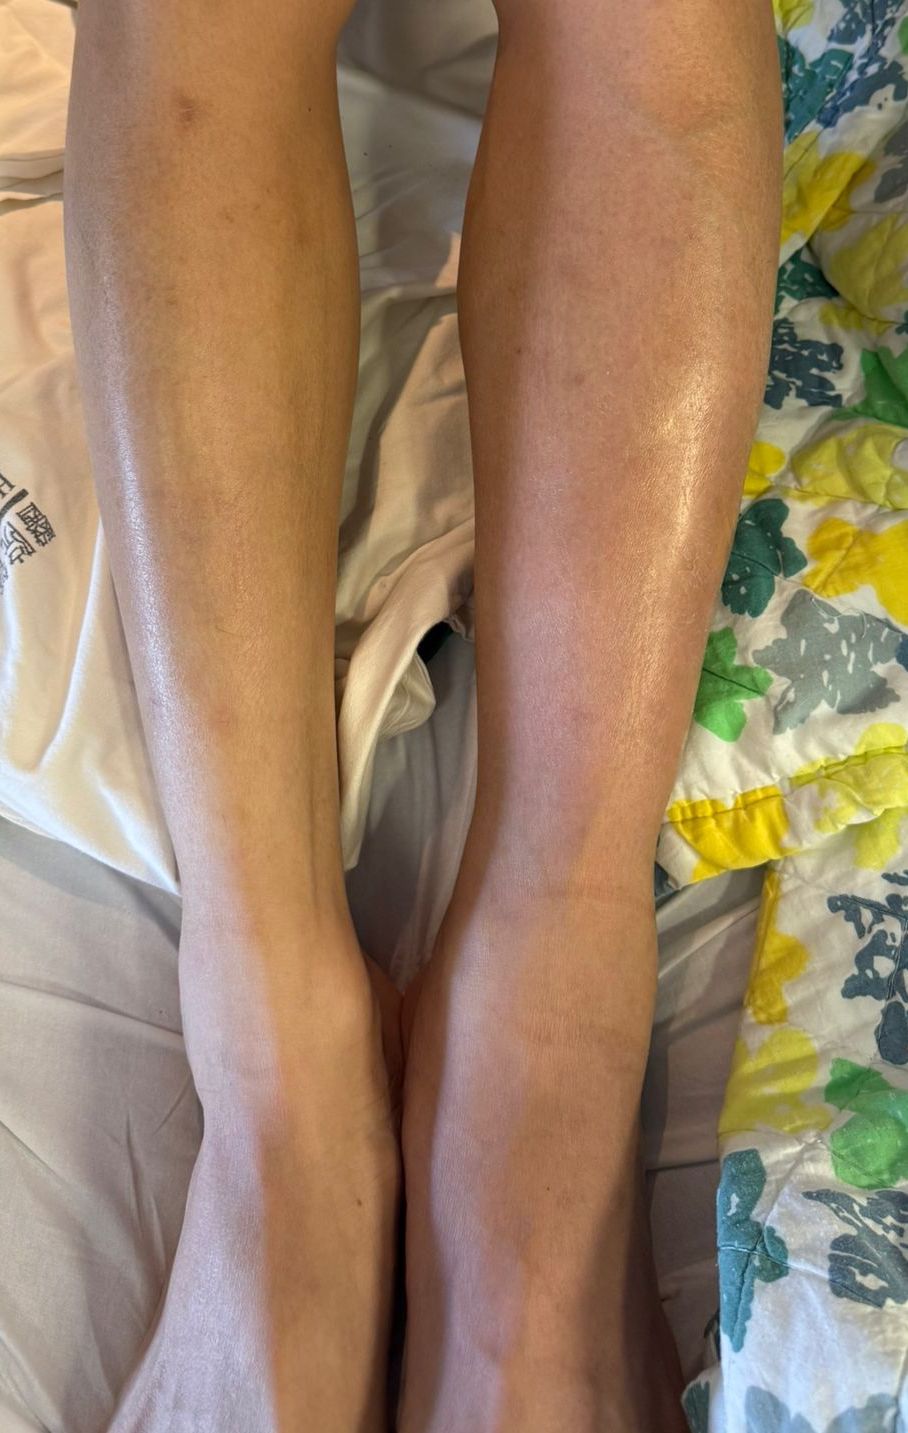

This was a 23-year-old gentleman with history of May Turner syndrome and protein C deficiency. He had history of left lower limb deep venous thrombosis from left common iliac vein to common femoral vein with mechanical thrombectomy and stenting done in 2022. He was on long term rivaroxaban. However, patient became a gym enthusiast in 2025 and was poorly compliant to anticoagulation treatment to avoid easy bleeding during exercise. He was admitted in August 2025 for left lower limb swelling.

Accesses at right and left popliteal veins were established. A FlowTriever disc was inserted as a temporary inferior vena cava filter via the right popliteal access. Wire was passed through the thrombosed left common iliac to femoral stent. Aspiration thrombectomy was performed and aspirated small amount of chronic blood clots. Subsequent, an "up and over" access was established with a 16 French aspiration catheter inserted through the right popliteal access to the left common iliac stent. The Clottriever catheter was inserted through the left popliteal access into the aspiration catheter. The Clottriever catheter was then retrieved, with simultaneous forward movement of the aspiration catheter to protect the collection basket of the Clottriever catheter from damaging the left common iliac stent during the retrieval process. Moderate amount of blood clots were retrieved with multiple attempts. Balloon angioplasty was then performed and blood flow through the common iliac vein was restored. There was significant improvement in terms of lower limb swelling after the procedure and the patient was discharged later with anticoagulation therapy.

This demonstrates endovascular thrombectomy via an "up and over" access to treat a case of recurrent deep vein thrombosis with a thrombosed left common iliac to femoral stent. The patient had a good recovery and there is no recurrence of deep vein thrombosis to date.